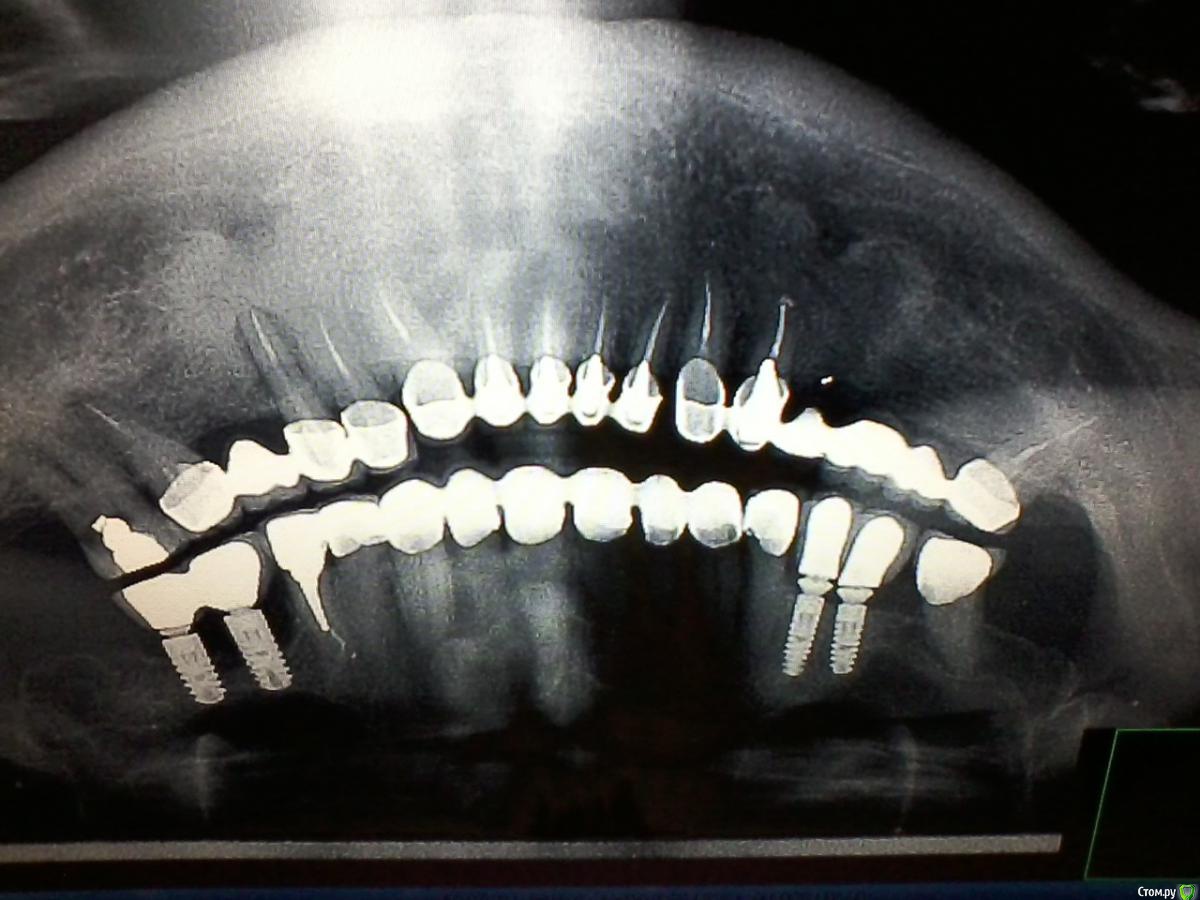

OLG Опубликовано 30 августа, 2016 Поделиться Опубликовано 30 августа, 2016 Здравствуйте,коллеги.Пациент из Америки ставил имплантаты давно. Может кто-то узнает, что за фирма? Ссылка на комментарий

OLG Опубликовано 30 августа, 2016 Автор Поделиться Опубликовано 30 августа, 2016 Извините, что кверх ногами. не знаю как перевернуть. Ссылка на комментарий

Доктор Добрых Дел Опубликовано 30 августа, 2016 Поделиться Опубликовано 30 августа, 2016 Астра вроде Ссылка на комментарий

pit Опубликовано 30 августа, 2016 Поделиться Опубликовано 30 августа, 2016 Здравствуйте,коллеги.Пациент из Америки ставил имплантаты давно. Может кто-то узнает, что за фирма?Анкилос 4 Ссылка на комментарий

IvanK Опубликовано 31 августа, 2016 Поделиться Опубликовано 31 августа, 2016 Анкилос+1 1 Ссылка на комментарий

Чертков Александр Опубликовано 31 августа, 2016 Поделиться Опубликовано 31 августа, 2016 Анкилос+1 Ссылка на комментарий

faity Опубликовано 31 августа, 2016 Поделиться Опубликовано 31 августа, 2016 +1 Ankylos Ссылка на комментарий